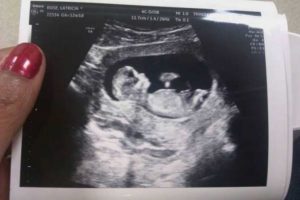

Прогрессирующая беременность 12 недель

• Размер плода к 12 неделе достигает 6 см, а весит малыш не более 13 гр. Несмотря на такие крошеные размеры, на фото эмбриона (плода) во время УЗИ уже четко видно, что внутри нас – настоящий человек: с головой, туловищем, тоненькими ножками и ручками.

Беременность в 12 недель означает, что развитие внутренних органов плода произошло и они продолжают расти дальше. К началу 12 недели размер плода составляет примерно 6 см. За эти 7 дней он подрастет еще на 1-2 см. Все основные ткани и органы малыша развиты, теперь он активно питается через плаценту. Это значит, что самый опасный период его эмбриональной жизни прошел.